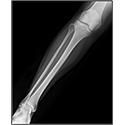

LOWER LIMB

Interactive Radiology